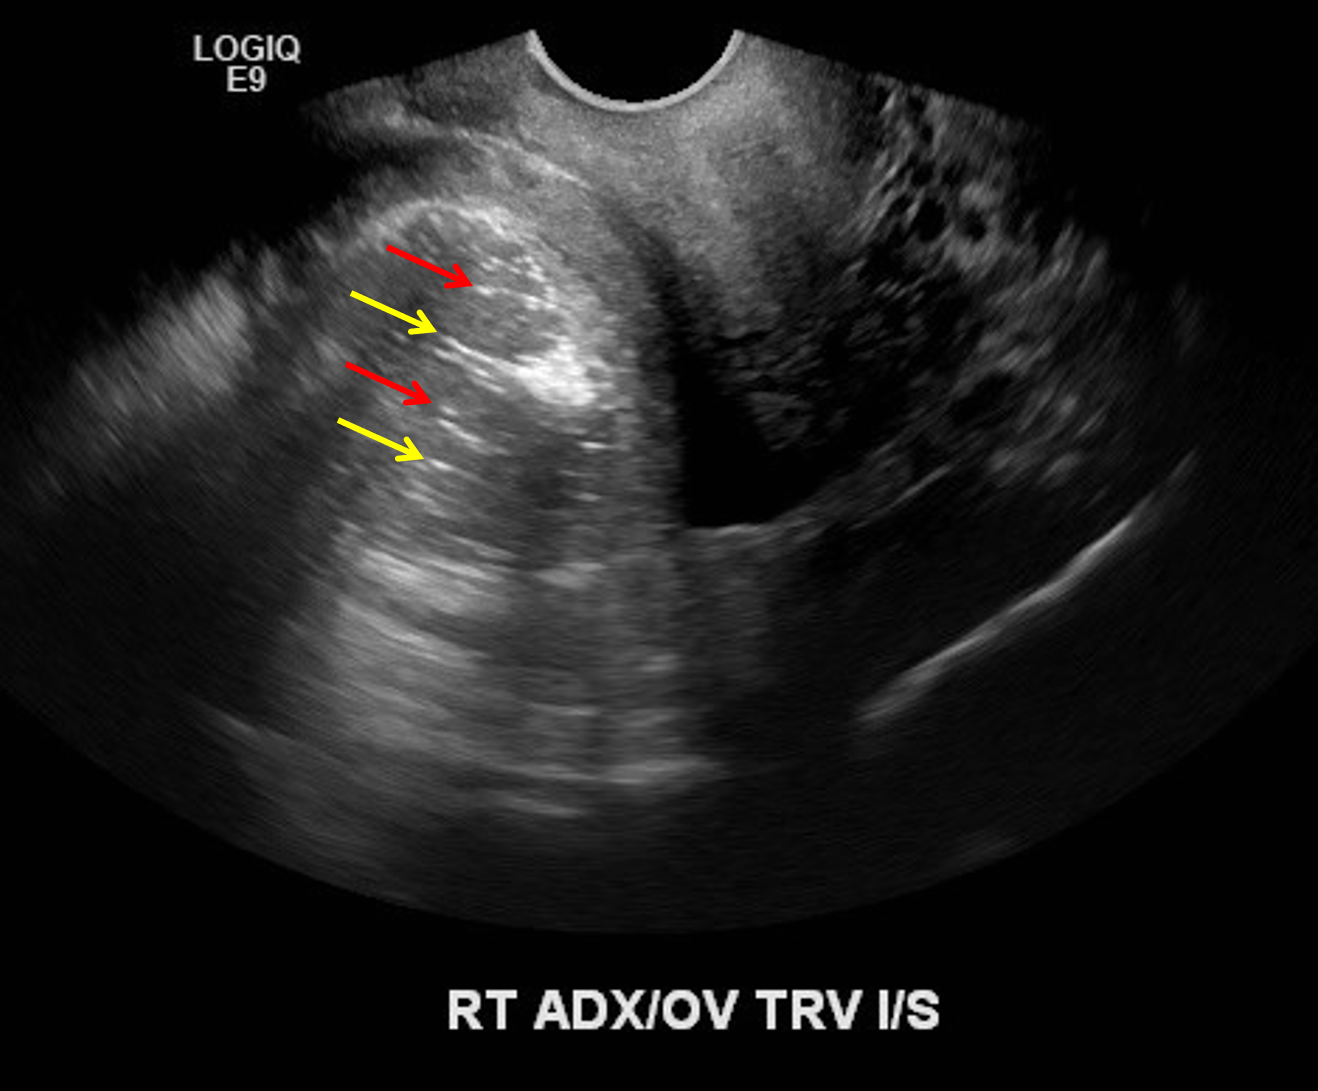

Sample ReportMarkedly enlarged right ovary with heterogeneous echotexture, peripheralization of ovarian follicles, and minimal internal vascularity, concerning for ovarian torsion.

Echogenic mass along the medial aspect of the right ovary with internal “dot dash” appearance is consistent with a dermoid cyst and is the likely lead point for ovarian torsion.